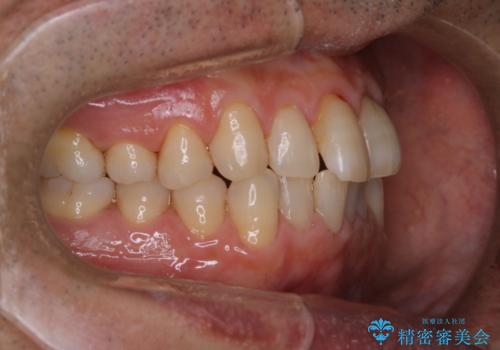

インビザラインでのマウスピース矯正中にPMTCで着色をきれいに

- インビザラインでの矯正治療中の方です。コーヒーをよく飲むため、着色が気になるとのことでした。PMTC60分コースを行いました。

PMTC(保険外治療)は、毎日の歯磨きで落としきれない汚れや、コーヒ、紅茶・タバコのヤニなどの着色も除去します。目には見えない歯と歯の間・歯肉の境目・インビザライン中はアタッチメント周囲などに残っているプラーク(歯垢)もしっかり取り除きます。PMTCでは専門的な機械や材料を使用して、徹底的に汚れを除去するため、虫歯・歯周病・口臭予防などにつながります。

また、仕上げのトリートメントでは歯の表面の凸凹にミネラルを補給して、ツルツルの表面に仕上げます。定期的にPMTCを行うことにより、歯質の強化になり着色がつきにくい状態になります。